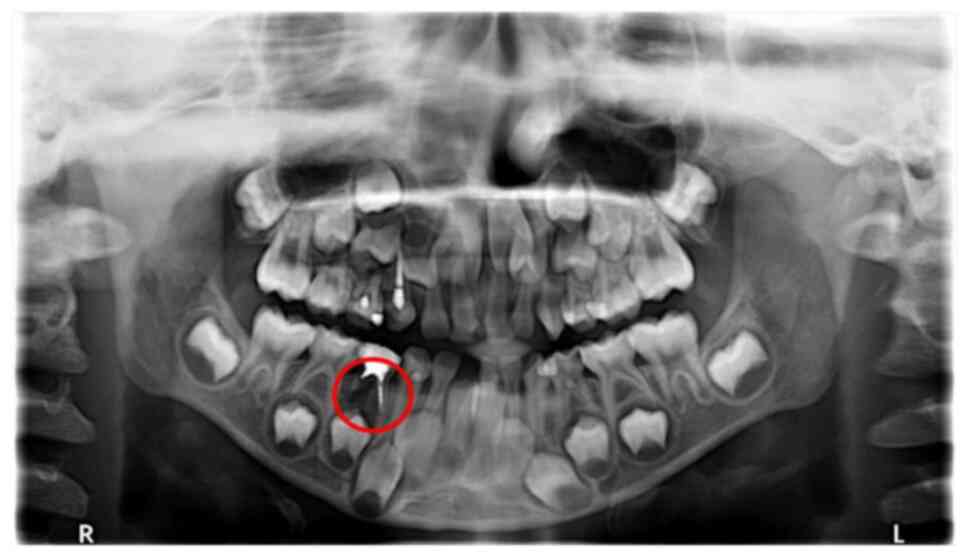

The efficacy of the treatments were evaluated 6 months after surgery. X-rays from Group B were used as examples for efficacy evaluation. No abnormal images were detected of the root and germ of the permanent tooth of the left lower second deciduous molar, which indicated effective treatment 6 months following surgical treatment (Fig. 3). Conversely, the distal root resorption of the right lower primary molar displayed a low periapical density shadow, thus was recorded as an ineffective treatment (Fig. 4). The observation of treatment outcomes at 6 and 12 months post-treatment reinforced the distinctions demonstrated between the various treatments applied in the present study. Imaging of the effectively treated teeth exhibited normalcy in the periapical region, whereas ineffectively treated teeth demonstrated significant abnormal shadows. These results highlighted the role of research in assessing therapeutic effects in clinical applications and may offer practical insights for the long-term management of periapical inflammation of deciduous teeth.

Figure 3

No abnormal images taken from group B (the encircled root was clear with no resorption) were found in the root and permanent tooth germ of the left lower second primary molar.